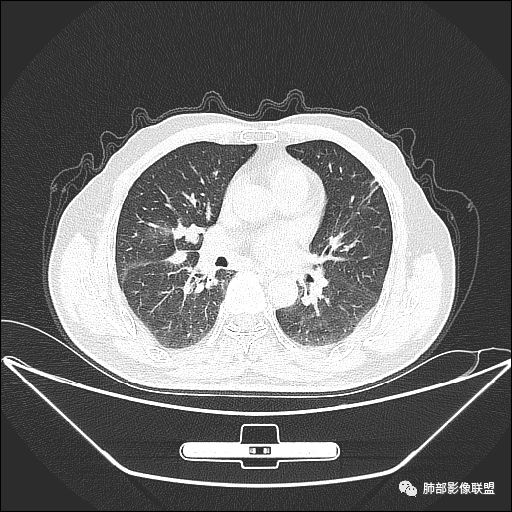

入院CT

老年男性,亚急性病程,咳嗽咳痰。右肺中叶团片影,外朝内分布,大部分边界清楚平直,内侧支气管进入,团片影见低密度坏死区,强化明显,延迟强化,血管破坏不明显,符合爬行征5个特点:

1.肺外周生长。

2.外侧部分体积大于内侧。

3.病变最大径与肺的纵轴及水平面任何一条轴线不平行。

4.病变内侧支气管通畅。

5.病变区域肺容积无缩小。

双侧肺门及纵隔淋巴肿大并可见钙化。考虑结核,但部分边缘膨隆,肿瘤待排。

老年男性,因“咳嗽咳痰1月余。”入院。病程中咳嗽咳痰,咳黄白痰,间断咯少许鲜红色痰血。PPD阳性。胸CT:右肺中叶外侧段支气管管腔阻塞,大片实性病变,病灶边缘光滑,部分边缘膨隆,可见分叶,肺门及纵隔可见肿大淋巴结,并可见钙化。增强可见病灶明显强化,而且延迟强化明显,病灶内多发低密度区,内见血管影,血管变细、部分血管破坏。考虑恶性病变可能性大,鉴别慢性肉芽肿性病变。

右肺中叶外侧段管腔阻塞、实性病变,病灶边缘光滑,可见分叶,肺门及纵隔可见肿大淋巴结,并可见钙化。增强可见病灶内多发低密度区。

老年男性,咳嗽、咳痰1月余,间断血痰。PPD阳性。

胸CT:跨叶大肿块,主体在中叶,右中叶外侧段支气管阻塞,病灶部分边缘膨隆,可见分叶,部分边缘平直,肺门及纵隔可见肿大淋巴结。增强病灶不均匀强化,延迟强化明显,病灶内多发低密度区,内见血管飘浮,部分血管变细、模糊。考虑:恶性病变可能性大,大细胞?淋巴瘤?鉴别慢性肉芽肿性病变。

右肺中叶软组织肿块,外围向内生长,叶间胸膜向前内移位,肿块近肺门侧跨叶,中叶外侧段支气管截断,密度不均匀,双侧肺门及隆突下见肿大淋巴结,增强后呈中度不均质强化,肺动脉供血,多发坏死区,边界尚清,坏死区域内见结构,结合病史考虑恶性,鉴别诊断1结核,爬行征是沿支气管树分布,外宽,内窄,周围有卫星灶,内气管狭窄后扩张,此例沿叶间胸膜长轴分布,气管有截断,不典型。2炎性肉芽肿,符合的地方下方层面增强后延迟性轻度环形强化,不符临床无发热等急性感染病史,实验室指标不符,病灶周围渗出及慢性炎性改变有,不明显。

主病灶在中叶,但是左肺舌段叶有条索影,陈旧病变。蓝色箭头支气管受压,是淋巴结肿大

主病灶在中叶,但是还有结节状病变在下叶

虽然是一个大的病灶,但是周围是比较散

边缘还有多发小灶

淋巴结肿大,钙化。

病灶明显平直,中央是粘液栓,低密度,分界清楚

综上,考虑炎症,结核。